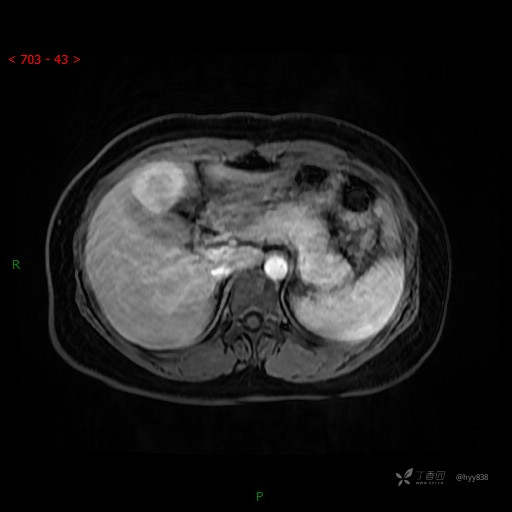

动态增强(动脉早期、动脉晚期、门脉期)